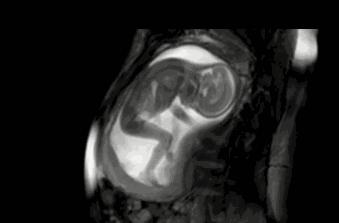

母爱的本能,会从怀孕开始。得知自己怀孕的消息后,每位女性会自动进入母亲的角色。

胎儿在孕妈的体内,通过脐带从母体内过的营养和氧气,以获得发育和成长。差不多到了28周的时候,他们已经具备基本的吞咽能力。

“羊水是胎儿的生活环境,为了锻炼自己的吞咽能力,胎儿会通过吞咽羊水的方式。而当吞咽的太急的时候,就会导致“打嗝儿”情况的出现。”